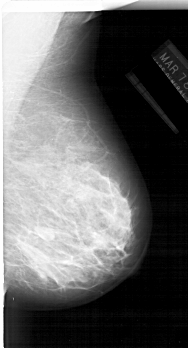

A_1233_1.LEFT_MLO

LEFT_MLO LINES 6736 PIXELS_PER_LINE 3436 BITS_PER_PIXEL 12 RESOLUTION 43.5 OVERLAY